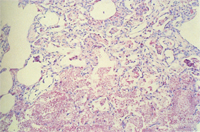

組織病變: 許多肺泡可見顆粒狀、泡沫狀、嗜酸性之無組織結構物質不規則散佈於肺泡中,間 雜肺泡巨噬細胞,少量嗜中性球,圍小支氣管及圍血管淋巴球及漿細胞增生,肺泡第二 型細胞增生(圖2,3)。